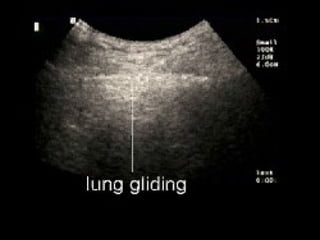

Left panel: Pleural line and A line (real-time).

The pleural line is located 0.5 cm below the rib line in the adult.

Its visible length between two ribs in the longitudinal scan is

approximately 2 cm. The upper rib, pleural line, and lower rib (vertical

arrows) outline a characteristic pattern called the bat sign.

Normal lung surface Leftpanel: Pleural line and A line (real-time). The pleural line is located 0.5 cm below the rib line in the adult. Its visible length between two ribs in the longitudinal scan is approximately 2 cm. The upper rib, pleural line, and lower rib (vertical arrows) outline a characteristic pattern called the bat sign.